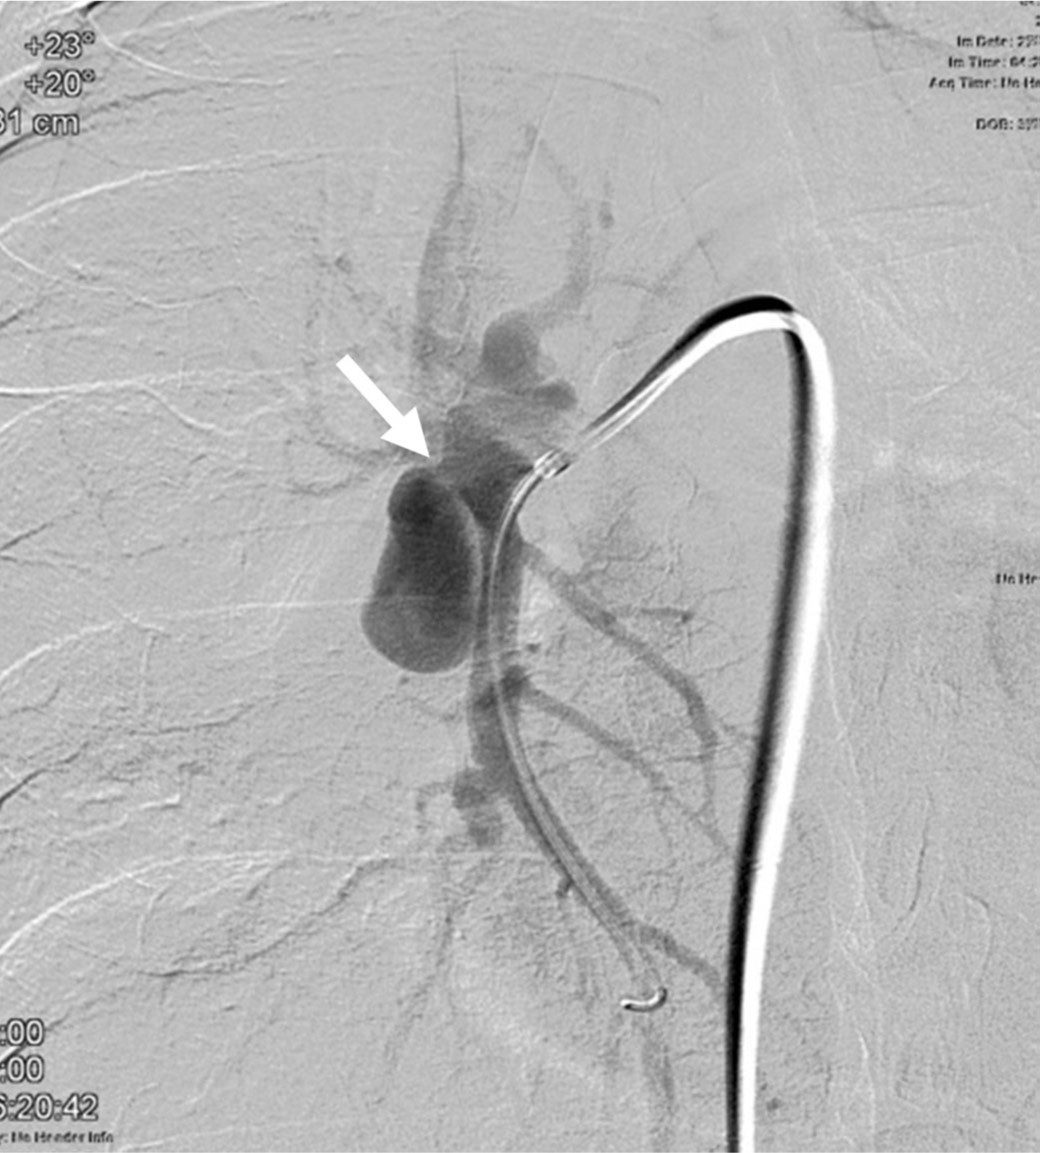

Fig. 2.

Fig. 2. Right pulmonary angiogram shows a pseudoaneurysm (arrow) at the proximal part of the right lower pulmonary artery.

Fig. 3.

Fig. 3. On selective angiogram of the right lower pulmonary artery with a properly angulated projection, the neck(arrow) of the pseudoaneurysm is clearly demonstrated.